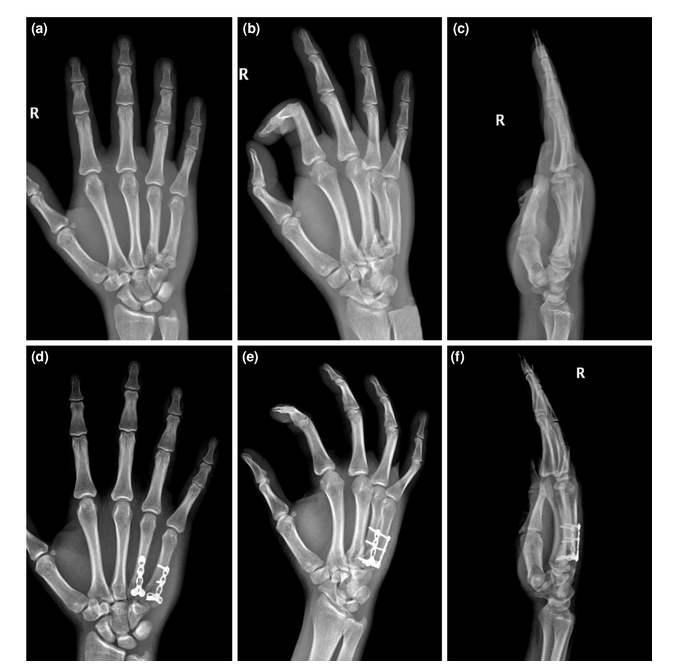

手术治疗患者的术前和术后影像;钢板固定的一个例子。(a-c)术前AP、斜位和侧位x线图像。(d-f)术后AP、斜位和侧位x线图像。